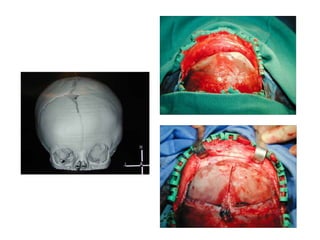

Fusión prematura de las suturas craneales

1 en 1.700 a 2.100 nacimientos

Incidencia 0.04%

La mayoría son eventos aislados (67%), no

síndrome

Sutura Craneal simple - Eleva la Presión Intracraneal

14%

Sutura sagital más común: alrededor del 50%

Reparación antes de los 1 años: potencial de

osificación

IV Craneosinostosis

Forma de la cabeza estereotipada por sutura

involucrada

Sagital (50%): escafocefalia

Coronal (30%) Uni: plagiocefalia, bi: braquicefalia

(síndrome más frecuente)

Metopica / Frontal (10%): trigonocefalia

Lambdoidea (3%): plagiocefalia posterior

La edad de reparación optima varía según la sutura

Sagital 4 meses, Otras 6 meses